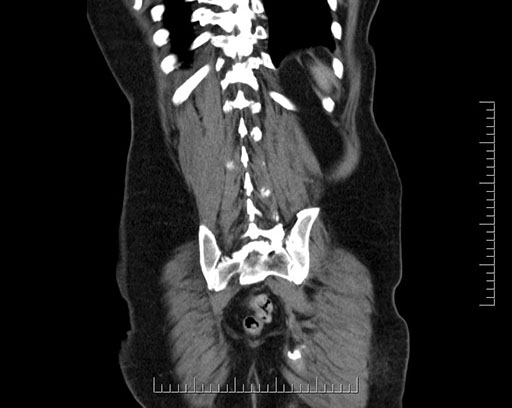

Imaging analysis